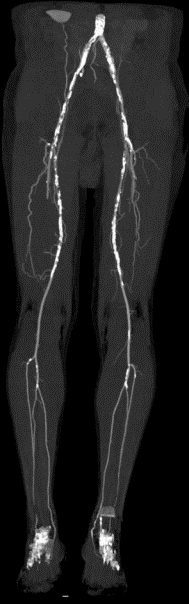

多普勒超声:右侧股浅动脉多发等至强回声斑块,中段闭塞,充满等回声。近段、远段多发充盈缺损。胫前、胫后动脉近段闭塞,胫后动脉远段由腓动脉供血。

术前CTA:右侧股浅动脉多节段重度狭窄、闭塞。

图片

术前造影:右侧股浅动脉中段重度狭窄、远端闭塞,膝下仅腓动脉通畅。

图片图片图片